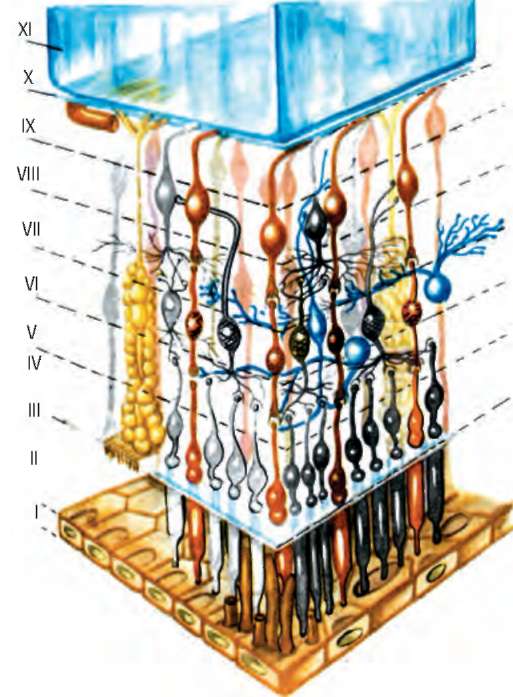

Рис. 1.3. Слои сетчатки (схема): I - пигментный эпителий; II - слой колбочек и палочек; III - наружная глиальная пограничная мембрана; IV - наружный зернистый слой; V - наружный сетчатый слой; VI - внутренний зернистый слой; VII - внутренний сетчатый слой; VIII - слой ганглиозных клеток; IX - слой нервных волокон; Х - внутренняя глиальная пограничная пластинка; XI - стекловидное тело